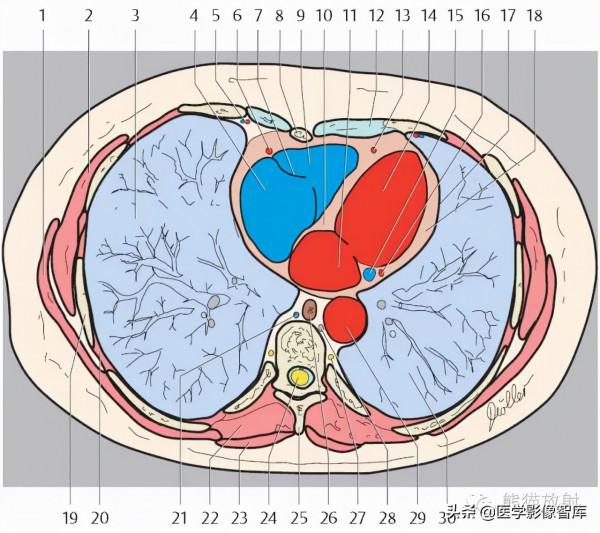

2. Rib 肋骨

3. External oblique muscle 腹外肌

4. Right hepatic vein 肝右靜脈

5. Inferior vena cava 下腔靜脈

6. Left hepatic vein 肝左靜脈

7. Diaphragm 膈肌